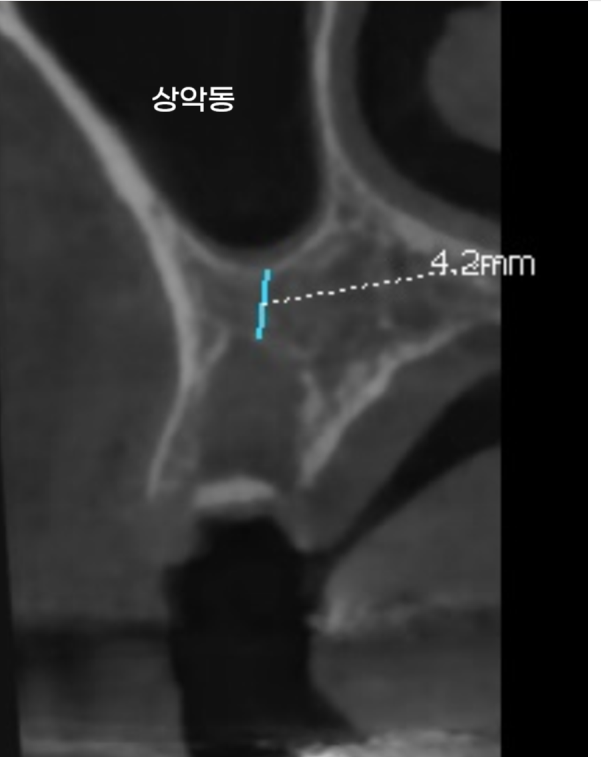

첫번째로 임플란트를 심기 위해

상악동 뼈를 들어올리는 과정에서

미세하게 점막이 손상될 수 있습니다.

250711 뼈 높이가 부족하여 상악동 거상술이 필요한 경우

이 부위는 코 안쪽으로 통하기 때문에,

뼈 속에서 생긴 작은 출혈도 코로 새어 나올 수 있답니다.